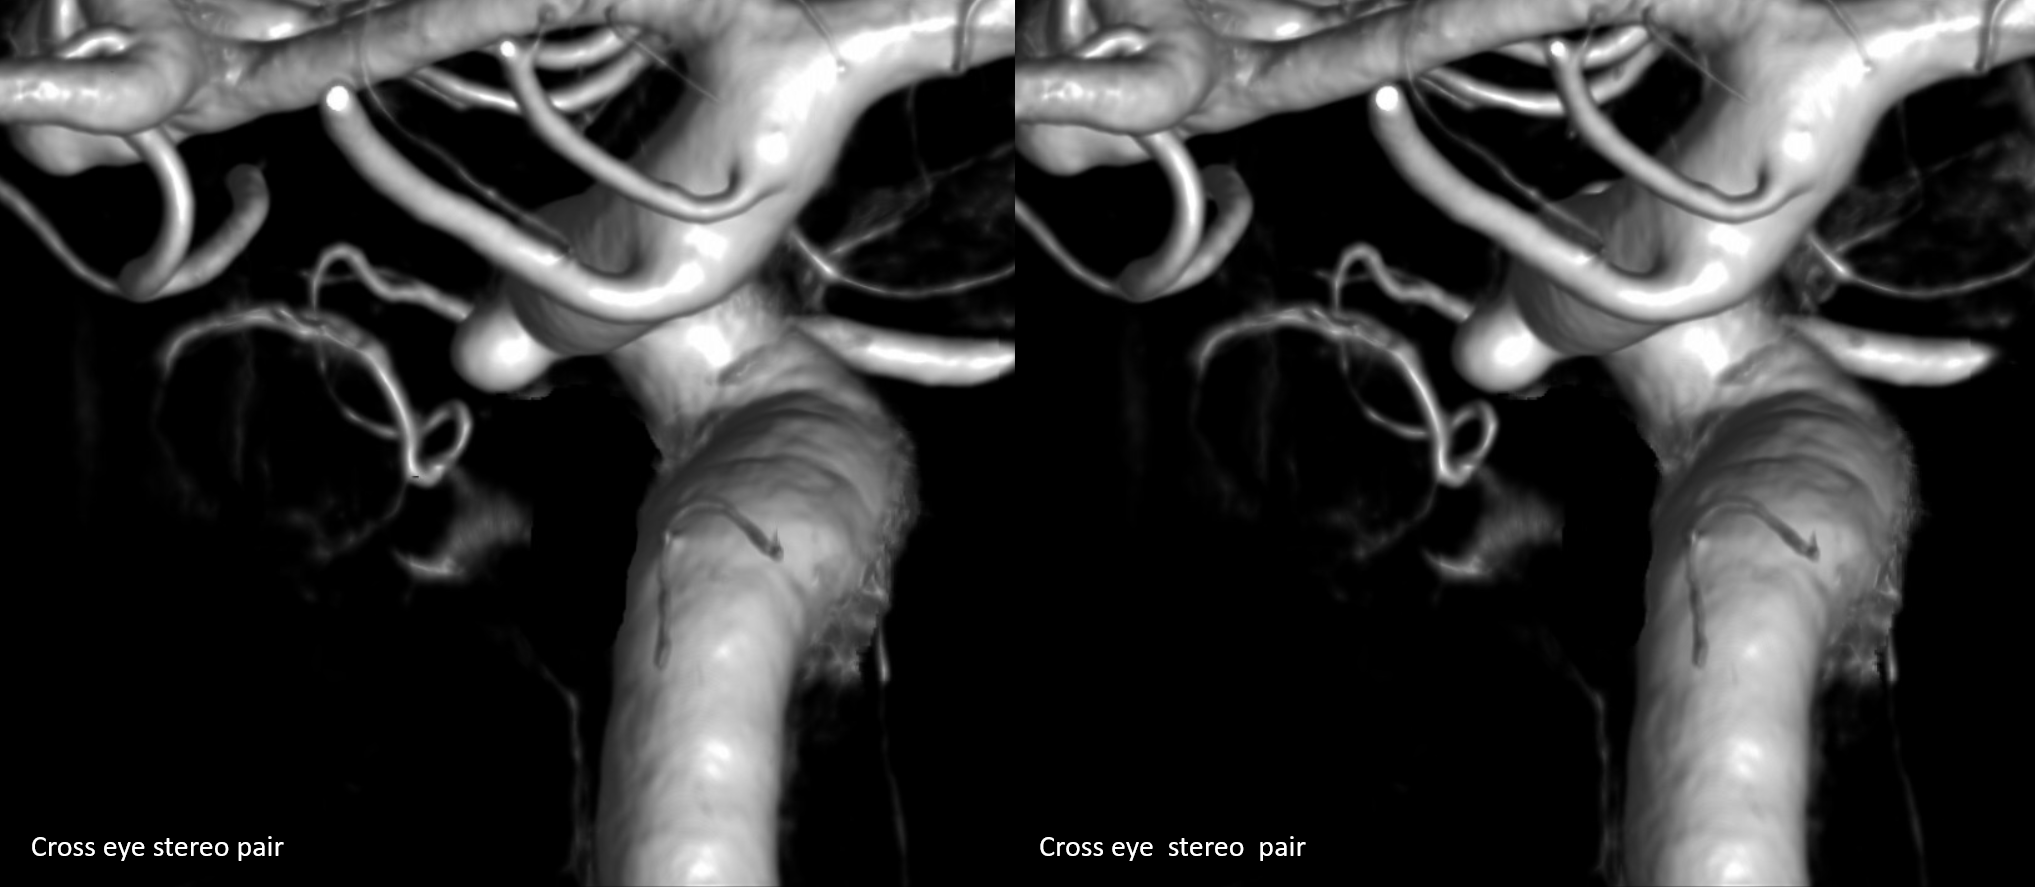

Stereos and MIPs. Both superior and inferior hypophyseals are well seen. The superior hypophyseal, despite being invisible on standard issue views, is quite large, even having two branches to the hypophysis.

Case courtesy Dr. Eytan Raz — here is a beautiful example of a very dominant superior hypophyseal artery (arrow) supplying the posterior hypophysis (arrowhead), with a correspondingly small inferior hypophyseal contribution from the MHT (dashed arrow)

View from the back — again small inferior hypophyseal, big superior hypophyseal — balance again… See the beautiful vascular ring of the posterior pituitary — the connecting it with the contralateral side

Cross-eye stereo

MIP image shows the sella nicely — and helps prove its posterior pituitary

Of course, there is an aneurysm here — the branch point camp would point out how this larger than usual branch is a setup for aneurysmal formation. Naturally…